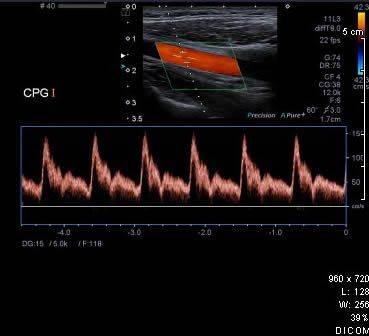

Le doppler peut être associé à l’échographie. Au cours du doppler, les flux des vaisseaux sont codés en couleur selon leur direction et leur vitesse, la mesure des vitesses et des résistances vasculaires est effectuée.